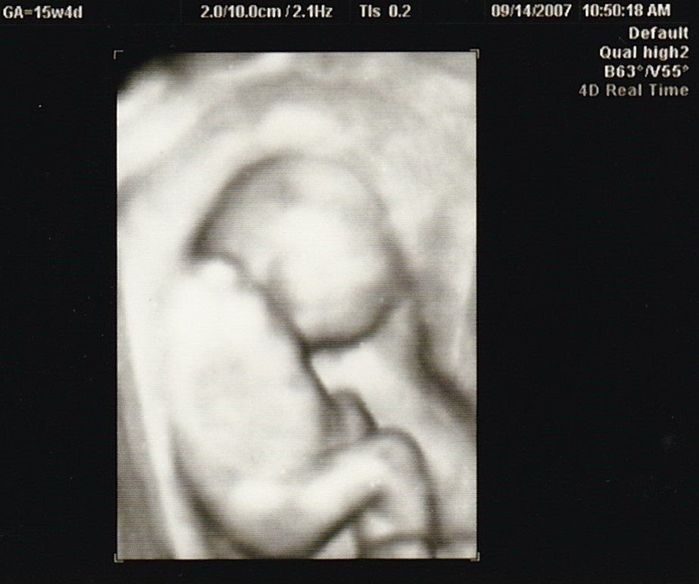

妊娠15週目のエコー写真

やっと安定期に入りました。「性別は、次回の検診のときに聞きたければ教えますよ」と言われていて、今回“男の子”と教えてもらいました。手で目をこすっているような様子など、かわいいな、早く会いたいな、名前どうしようかな、と思いを巡らせていました。退職したため、夫の休みに出産前最後の旅行もしました。